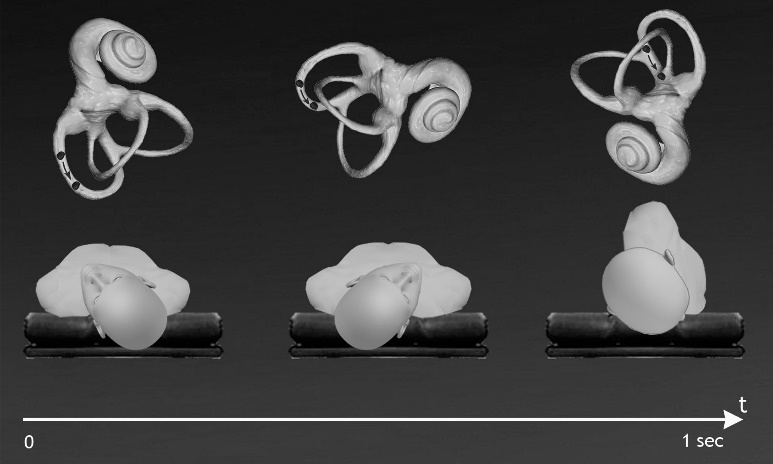

In 2003 we proposed the "Quick Liberatory Rotation Maneuver" 18 (QLR) for treating posterior canal BPPV; QLR uses the speed of execution of SM but performs the movement in the frontal plane, as in EM (Figure 1). In a comparative study of efficacy in the short and medium term between QLR, Parnes maneuver19 and SM, we demonstrated the equal clinical efficacy of these treatments 18. Our maneuver, based on a quick rotation of the head and the body of the patient, has been replicated by other Authors: “hybrid approach through Gans maneuver” 20, “hybrid maneuver” 21. Our original paper is not cited in these articles.

Figure 1.The “Quick Liberatory Rotation” maneuver for left posterior canal BPPV